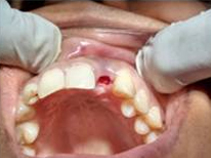

Pre Operation

Placement of Bone Grafting

Punch Cut